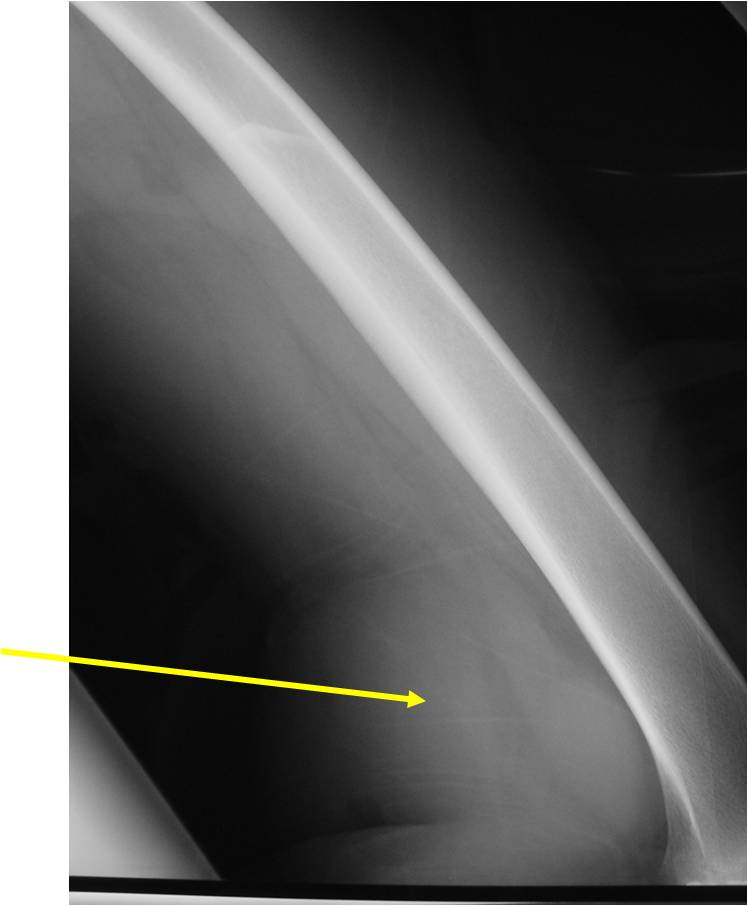

Radiographic Presentation

- Aggressive motheaten to permeative lesion

- Indistinct border in most cases

- Osseous destruction with a soft tissue component

- Chondroid matrix calcification may be present (60-70% of cases)

- Soft tissue mass

- Locally aggressive

- Cortical destruction in approximately half of cases

- Extension of tumor into adjacent soft tissues